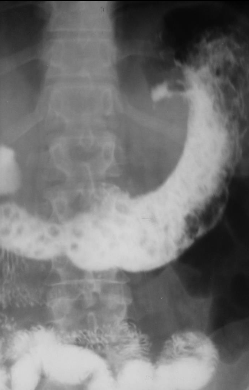

Polipoză gastrică